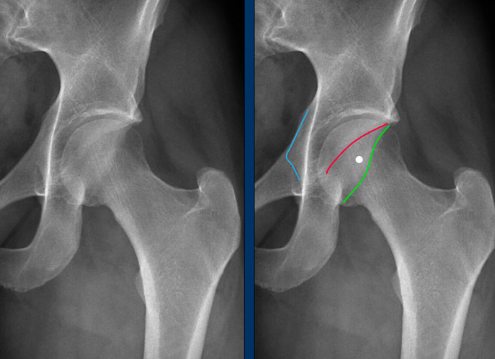

• Crossover sign - anterior wall extends lateral to the posterior wall

• Ischial spine sign - ischial spine projects more medially than normal into the pelvis

Normal hip - anterior acetabular wall (red line) is medial to the posterior acetabular wall (green line). Also note the ischial spine (blue line) isn’t overly projected into the pelvis

Abnormal hip - anterior acetabular wall (red line) extends laterally to the posterior acetabular wall (green line). Also note the ischial spine (blue line) isn’t overly projected into the pelvis